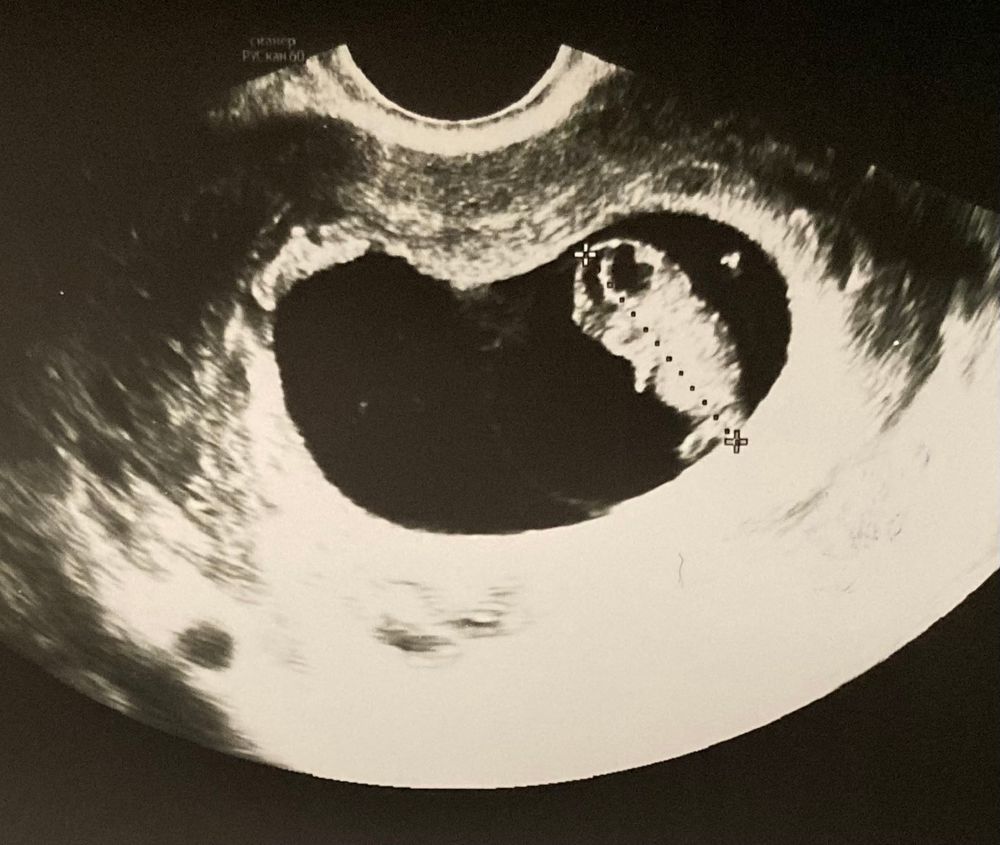

УЗИ 9 недель

По сроку сегодня 9+1, по узи 8+6 🤰🏻

ПЯ соответствует сроку

КТР - 21,7 мм

СБ - 179 ударов ♥️

Сегодня на узи показали, как пинается ножками 🥹